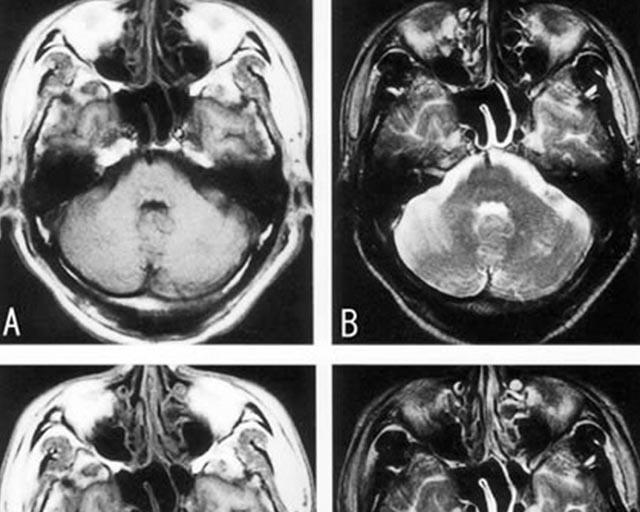

脳動脈解離

脳動脈がさけることにより、急性に血管の閉塞をきたすことがある。

特に椎骨脳底動脈系で生じやすく、若年者の脳梗塞の原因となる為、

若年者の頭痛を伴うワレンベルグ症候群を見た場合はまず脳動脈解離を疑う事が重要である。

頸部の過伸展やスポーツなどの外傷で生じる事がある。

画像所見はMRIでT1画像で動脈壁の三日月状高信号(壁在血栓)やMRAで

pearl and strings signやflap形成が見られる。